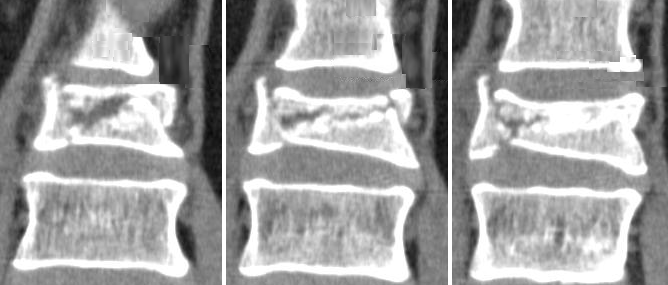

Рентгеновские снимки и медицинские изображения компрессионных переломов